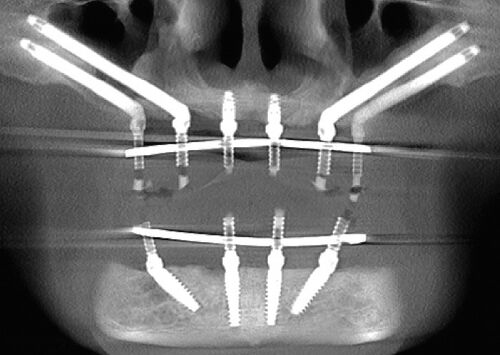

When a full set teeth replacement is required, certain dentists and specialists may often recommend six or more dental implants to support the prosthesis, and would undertake the treatment in multiple stages. all on 4 dental implants is di…

Recently, where ever I turn I see dental advertisements for all on 4 dental implants treatment. So what is it and is there a difference between various methods and the cost? “All-On-4” is a treatment concept that has evolved over the past …